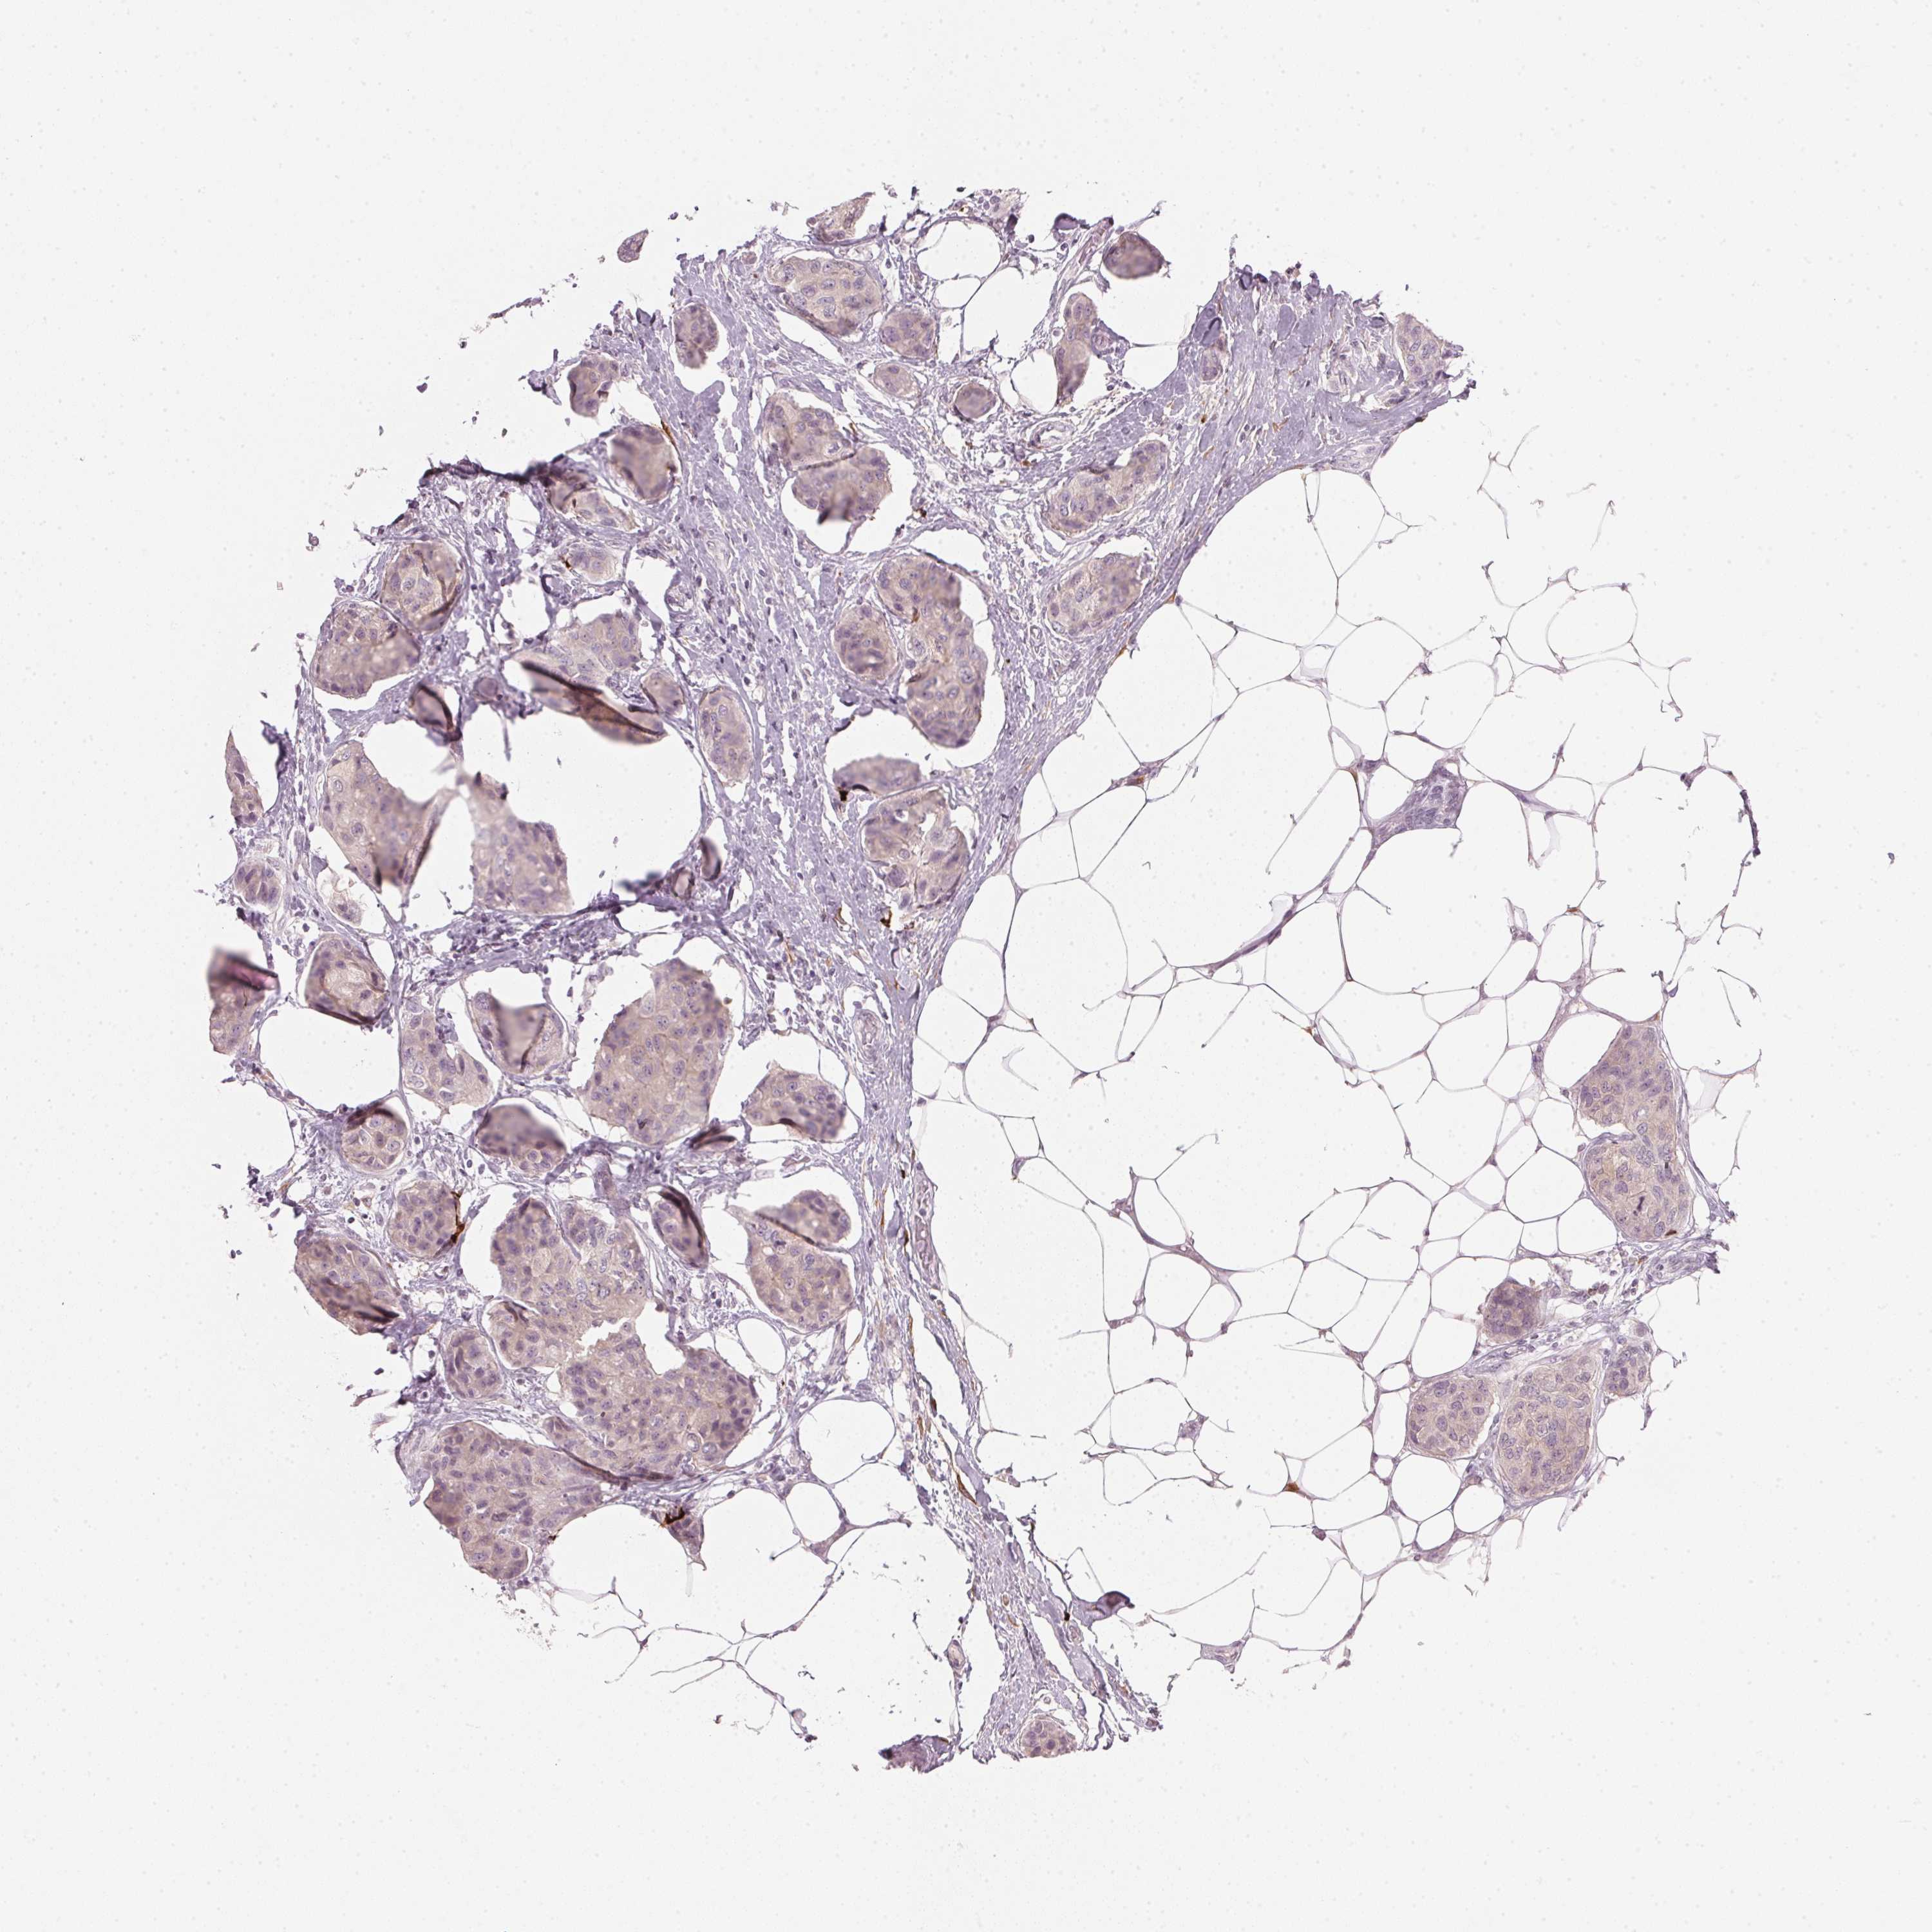

BRCA TCGA BRCA VALIDATION PROTEIN EXPRESSION

ANTIBODIES

AND

VALIDATION